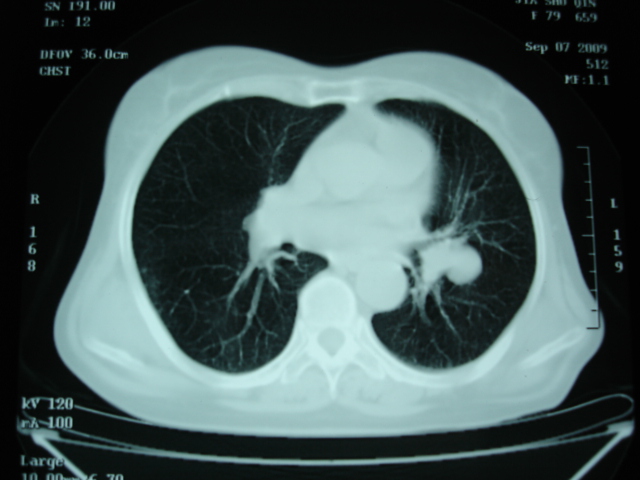

以下是引用卜一在2009-9-7 19:51:00的发言:[br][br] 1 左侧胸内甲状腺占位-多考虑甲状腺腺瘤! 2、左肺门占位-建议增强扫描以便明确性质。 3 慢支并感染! [br]

以下是引用shibing在2009-9-7 20:40:00的发言:[br]左侧胸内甲状腺占位-多考虑甲状腺腺瘤! 2、左肺门占位-建议增强扫描以便明确性质。 3 慢支并感染! [br]